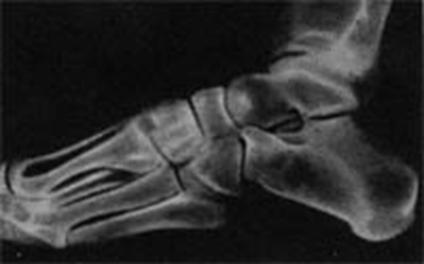

Рентгеновский снимок стопы человека. Затененные части - места основного расположения губчатого вещества